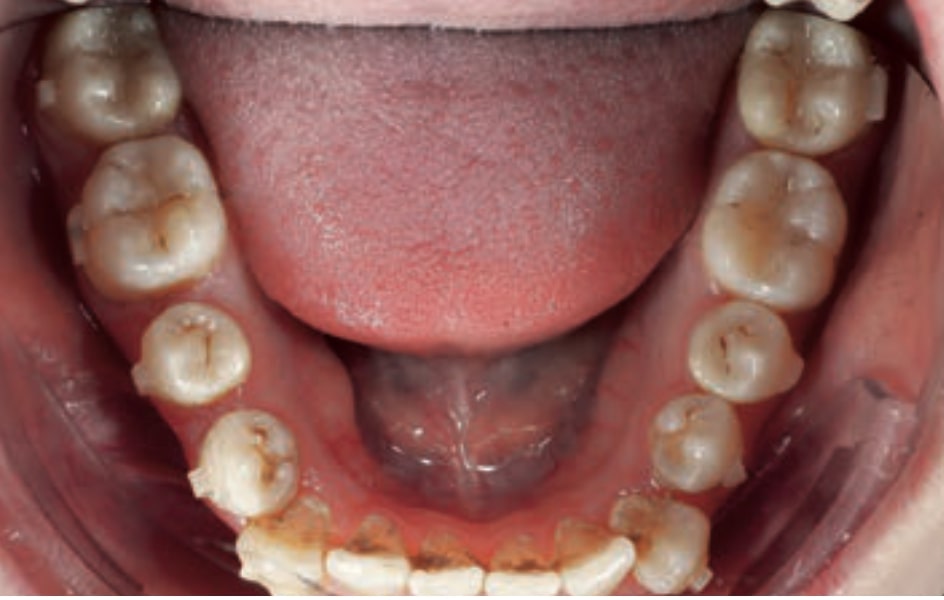

Chief complaint: The patient, a 19-year-old woman, was evaluated to undergo orthodontic treatment using the Angel Aligner Pro system. She presents with a skeletal Class III, mesofacial, with a dental Class III malocclusion and a 2 mm deviation of the lower midline to the left. Teeth 33 and 43 are out of the arch and cortical bone, with a crossbite issue on tooth 33. Fortunately, no functional issues affecting swallowing or breathing have been detected. The patient’s motivation for starting treatment was a general review of her dental and aesthetic health. The soft tissue analysis reveals mandibular protrusion that influences her facial profile. This diagnosis highlights the need for a comprehensive approach to address dental and skeletal misalignments, improving both the patient’s functionality and facial aesthetics.

• Dental Class III, 2 mm deviation of the lower midline to the left. 33 and 43 out of the arch and the cortical bone.

• Crossbite of 33.

• Treat existing cavities with dental fillings to guarantee the integrity of the teeth before starting orthodontic treatment.